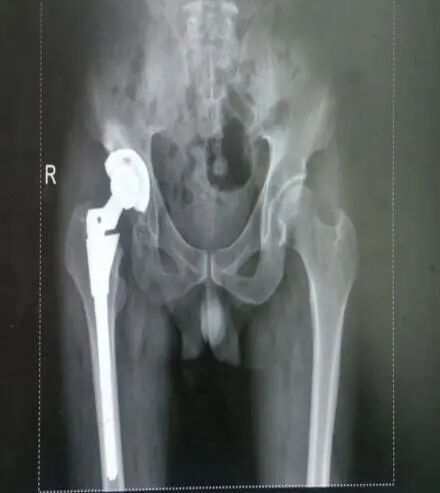

您是否經(jīng)歷過骨折的痛楚?

手術(shù)、住院、難以動彈

花時花費(fèi)花精力。

X線攝片只有在骨量減少達(dá)到30%以上后,才能通過X射線檢查出來,對于早期骨質(zhì)疏松癥狀很難發(fā)現(xiàn)。而該儀器對于診斷骨質(zhì)疏松、評估骨折風(fēng)險及骨質(zhì)疏松治療效果能得到精確評價。